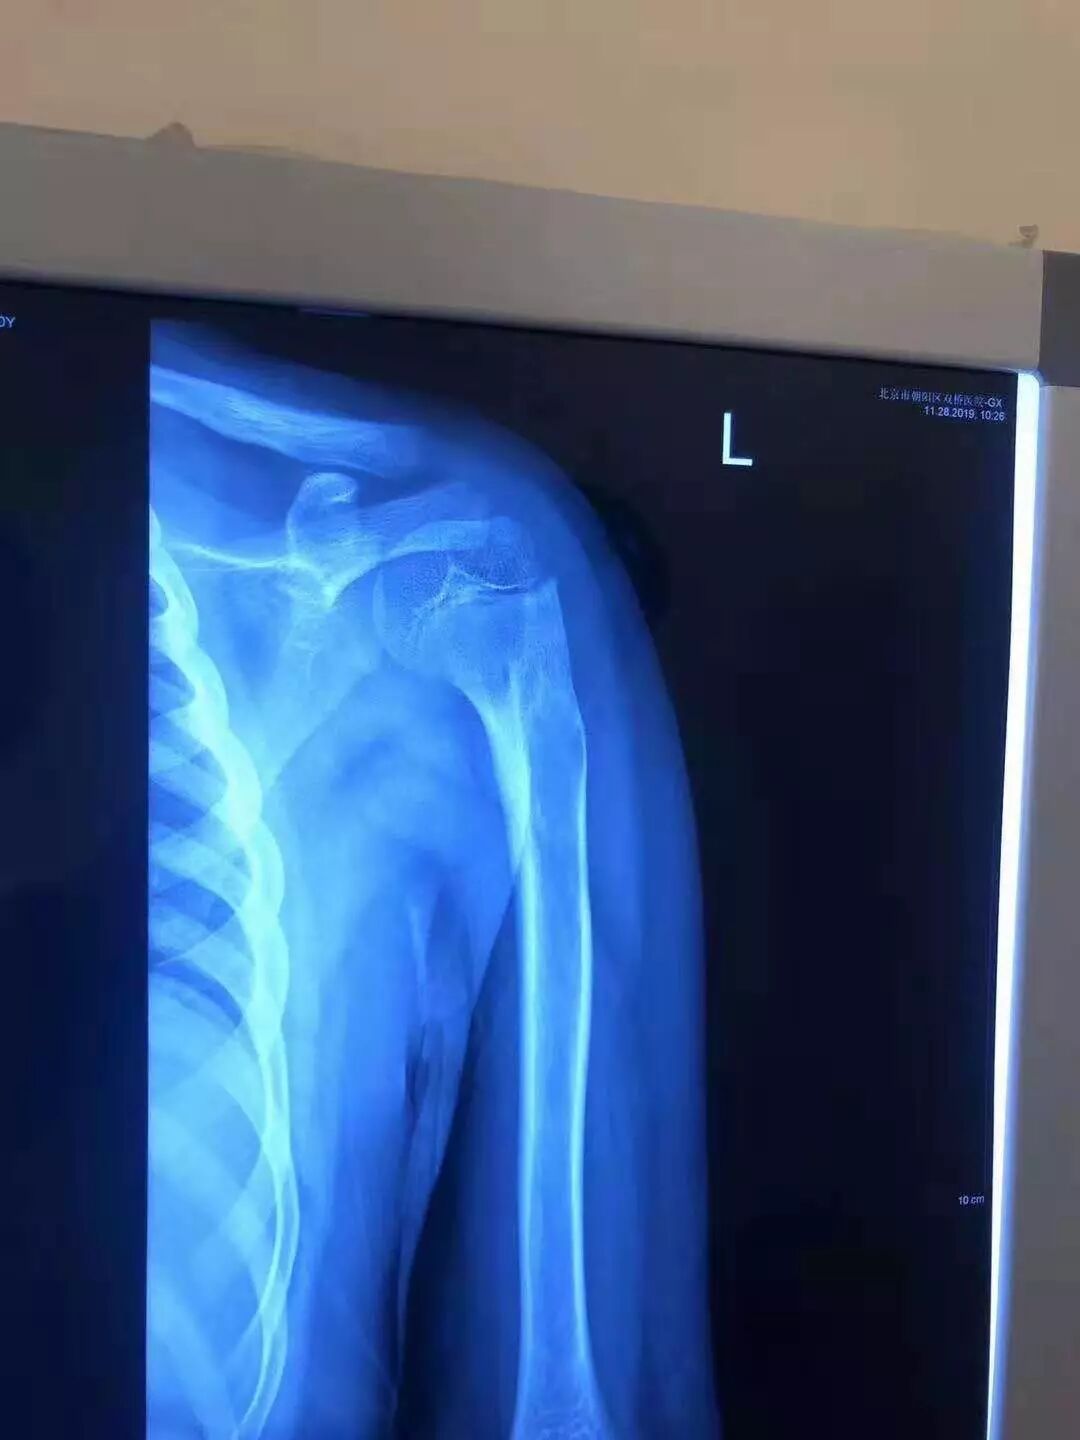

11月28日,小患者摔伤已经整7个半月了,王先生带着儿子到医院拍X片复查,小患者已经完全治愈。王先生一家对有明中医罗院长深表感谢。

11月28日小患者复查的X光片